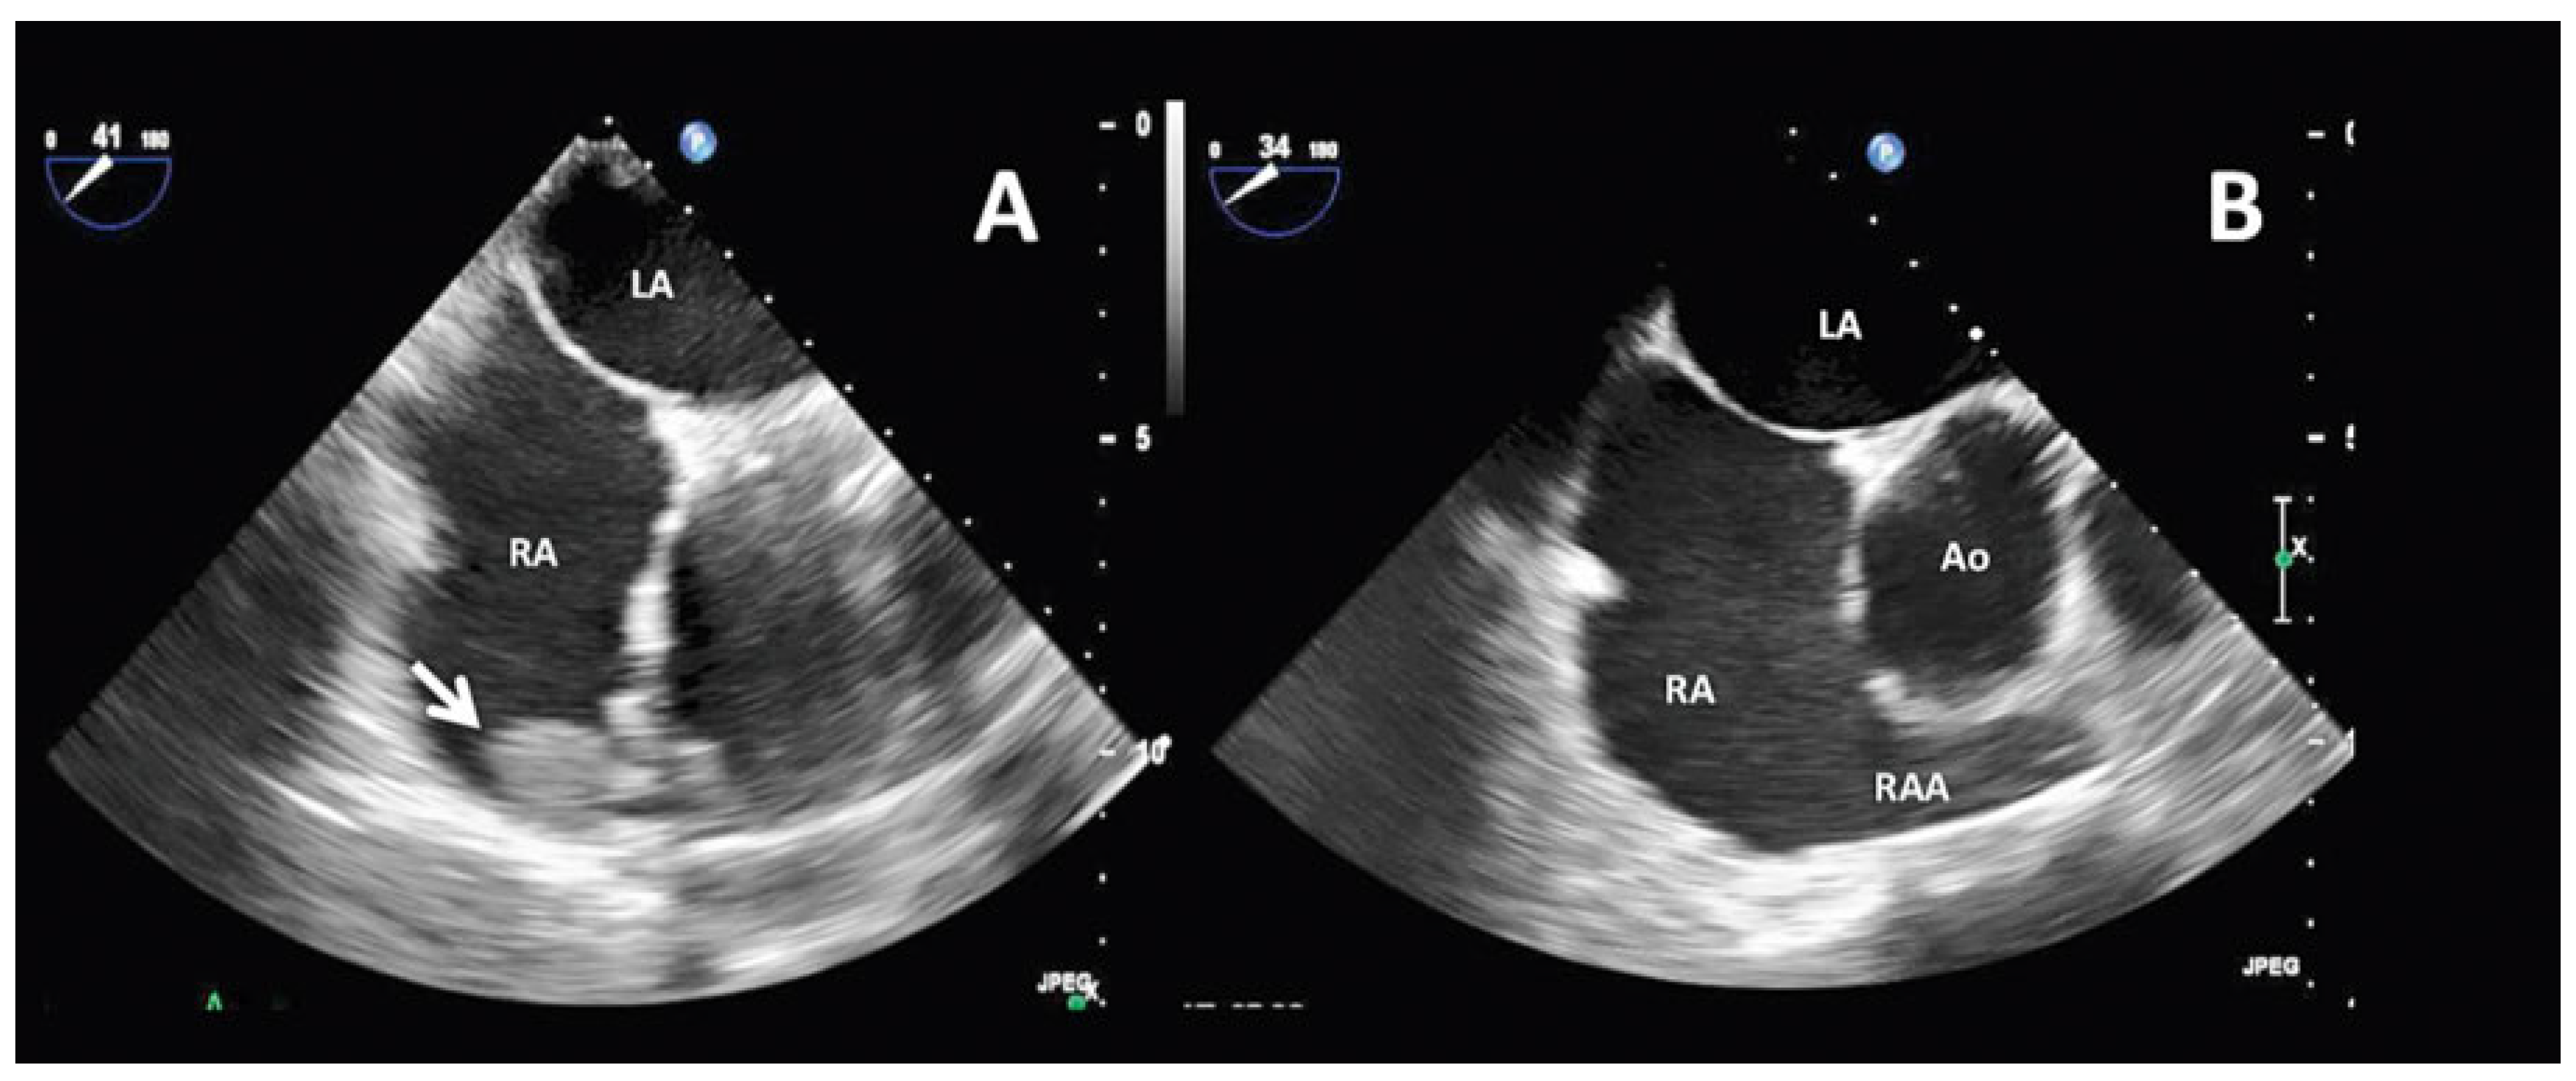

Case report